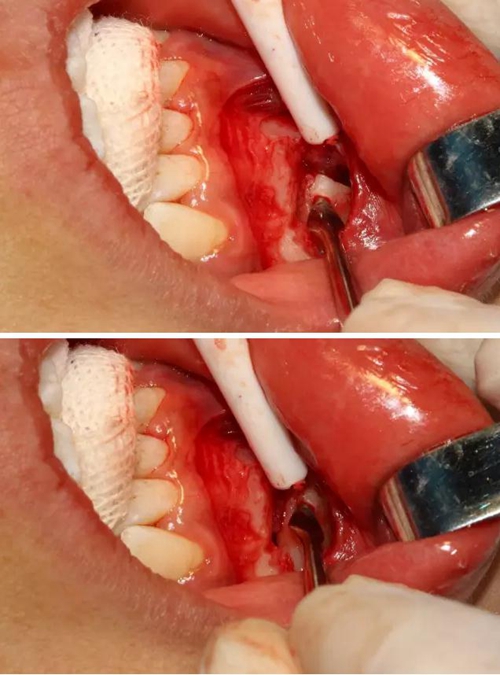

同時在剩余的根部斷面4MM下,預(yù)備2MM的溝槽,通過剝離子的三角尖端將牙體推出

三彎探針取出牙根部分

去除含牙囊壁